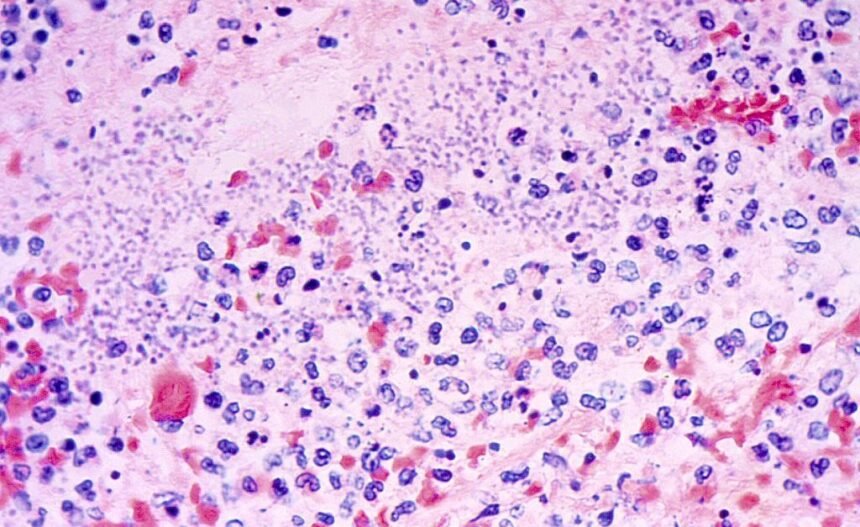

Pneumonic plague, which occurs when the bacterium Yersinia pestis gets into a personâs lungs, is both âthe least common and most dangerous type of plague,â according to the Cleveland Clinic.